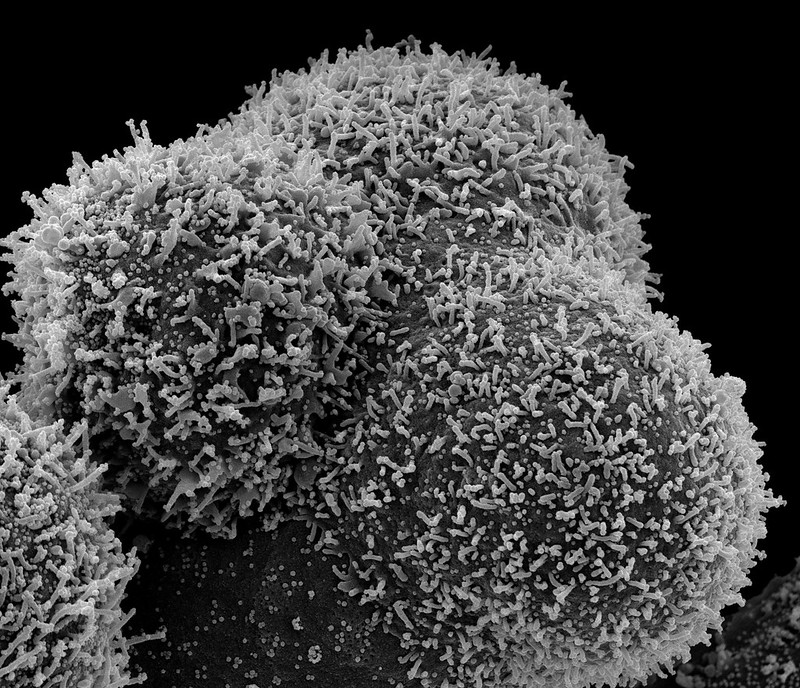

The National Institute of Allergy and Infectious Diseases (NIAID), part of the National Institutes of Health, today announced that the fourth iteration of the Adaptive COVID-19 Treatment Trial (ACTT-4) has closed to enrollment because the study met pre-defined futility criteria indicating that neither treatment regimen studied is likely significantly better than the other. The NIAID-sponsored trial aimed to determine which of two drug combinations—baricitinib plus remdesivir or dexamethasone plus remdesivir — was more effective at preventing adults hospitalized with COVID-19 on supplemental oxygen from progressing to requiring mechanical ventilation or death, among other outcomes.

Remdesivir (also known as Veklury) is an antiviral administered intravenously developed Gilead Sciences, Inc., of Foster City, California and is approved by the U.S. Food and Drug Administration (FDA) for the treatment of COVID-19 in hospitalized patients aged 12 years and older. Baricitinib (brand name Olumiant) is a modulator of inflammation administered in an oral tablet that was discovered by Incyte and licensed to Eli Lilly and Company based in Indianapolis. The FDA granted Emergency Use Authorization (EUA) for baricitinib in combination with remdesivir to treat suspected or laboratory confirmed COVID-19 in hospitalized patients aged 2 years and older who require supplemental oxygen, invasive mechanical ventilation, or extracorporeal membrane oxygenation. Baricitinib also is being studied in combination with standard of care therapies, including corticosteroids. Dexamethasone is a corticosteroid administered intravenously that is available as a generic drug. It has been recommended by the NIH Treatment Guidelines Panel for use in people hospitalized with COVID-19 who require supplemental oxygen based on evidence from clinical trials showing it can improve survival in this population.